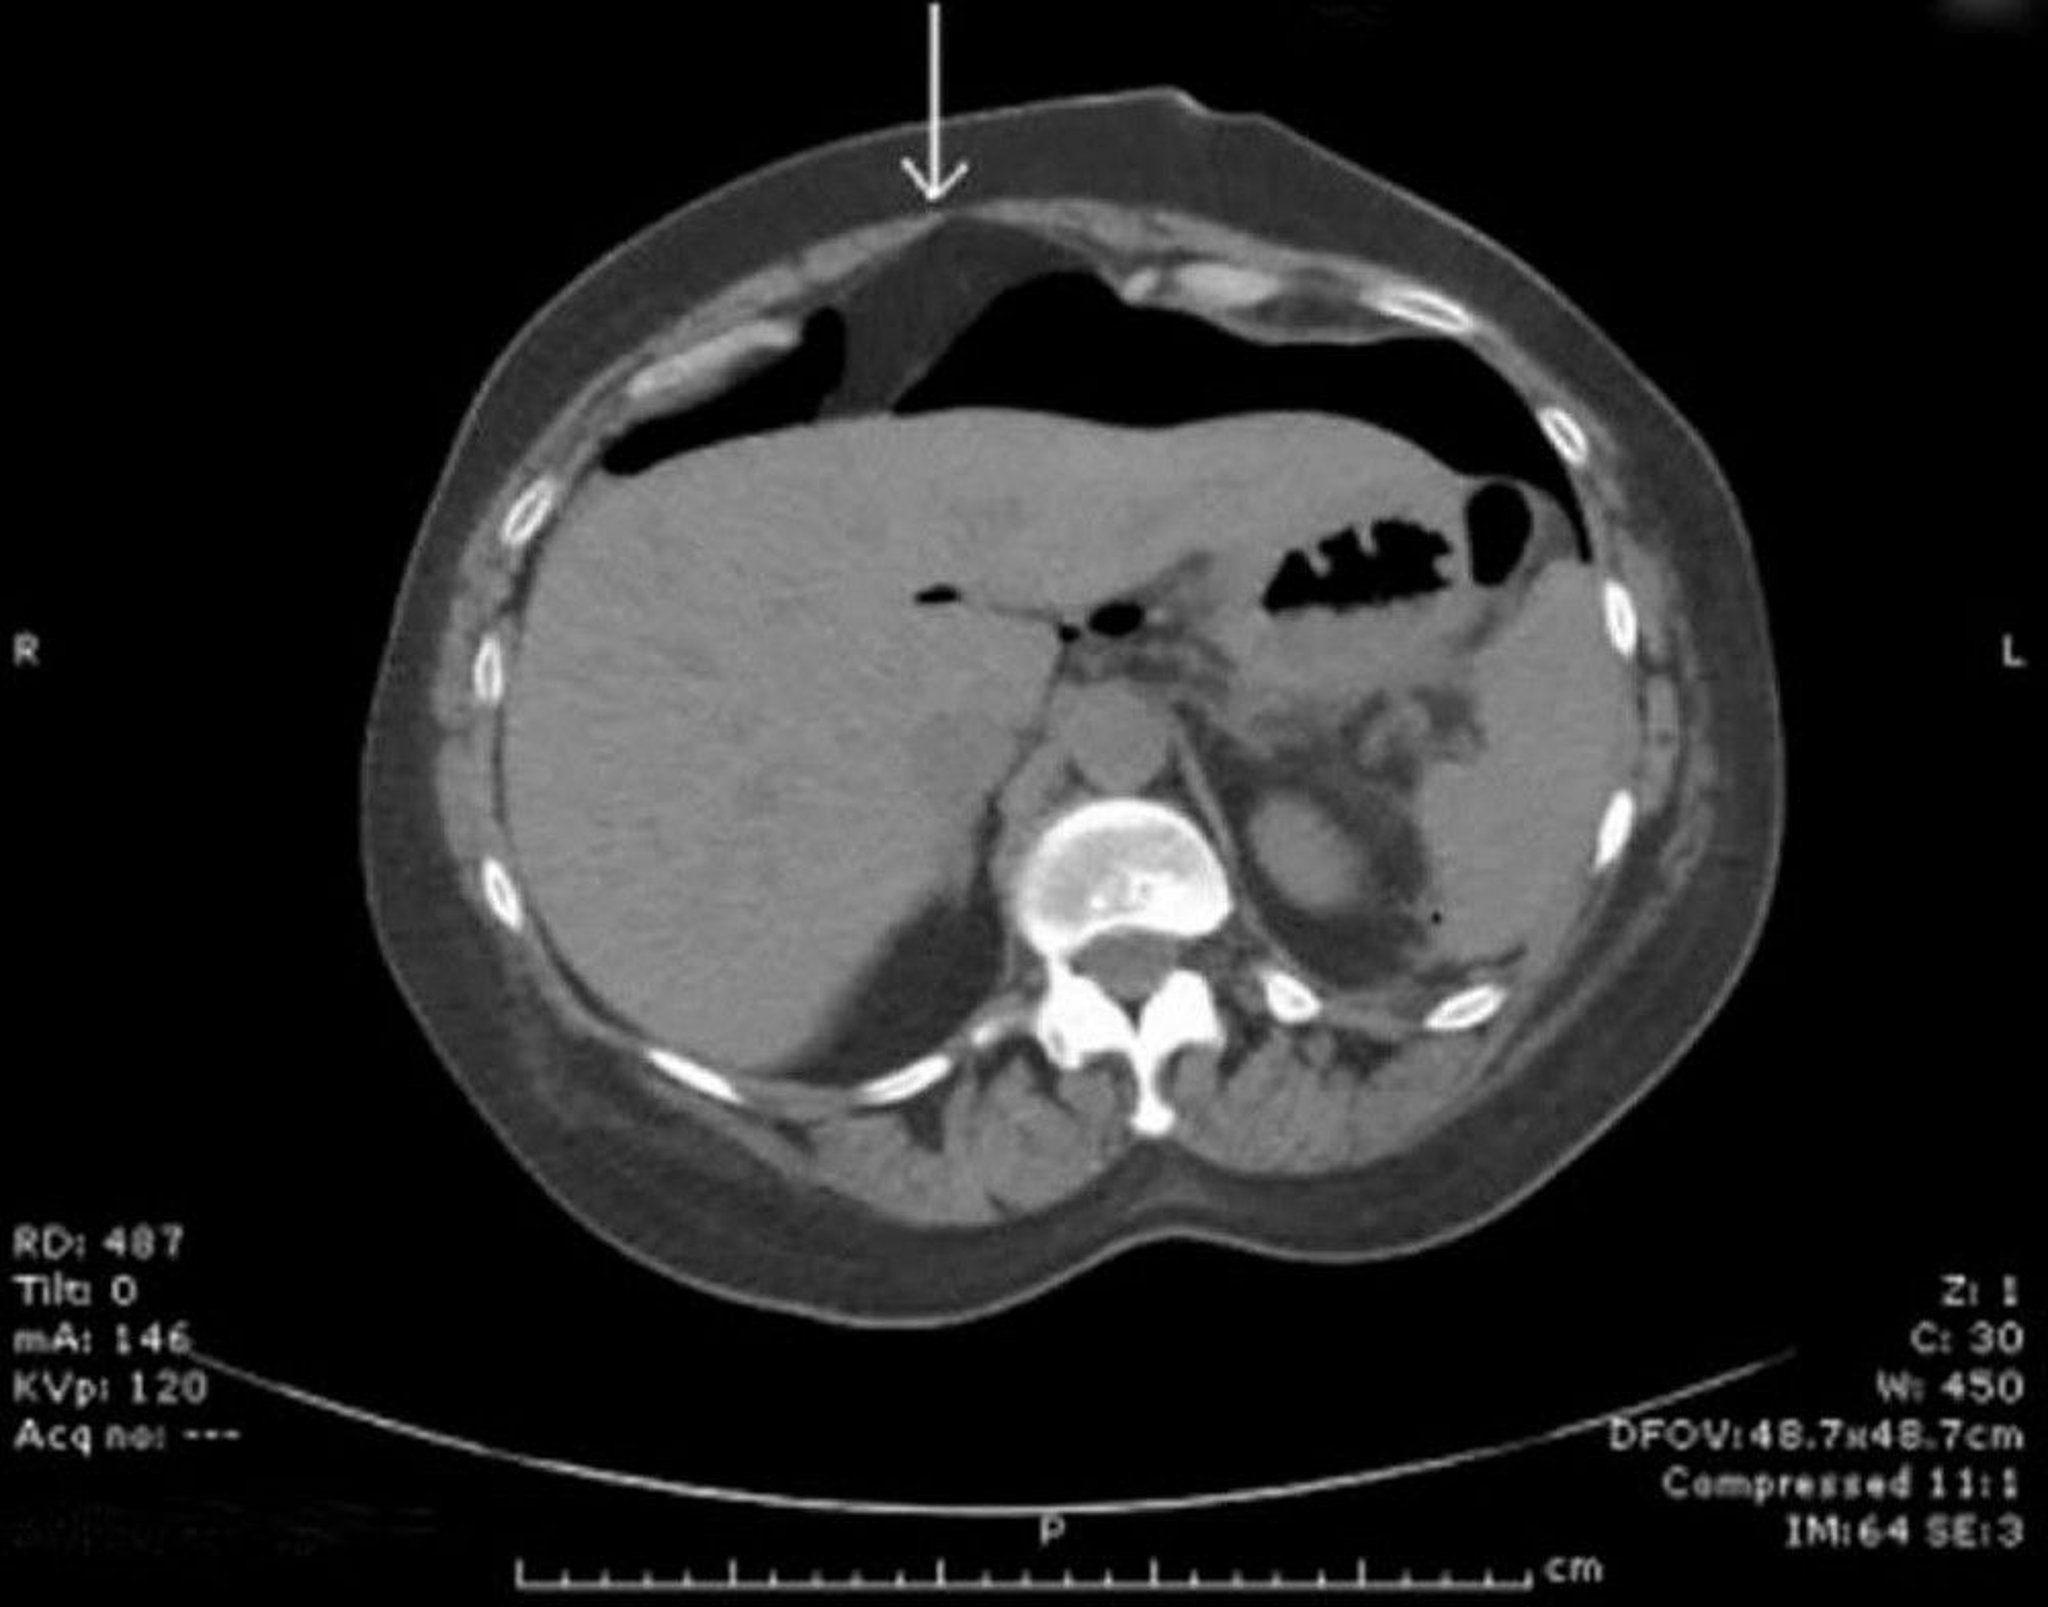

CT With Free Peritoneal Air

Free air is seen anterior to the liver. The arrow points to the falciform ligament.

Image provided by Parswa Ansari, MD.